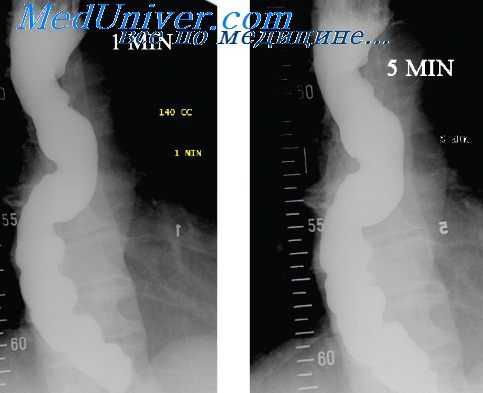

Рентгенологическая картина при воспалительных процессах в пищеводе слагается из патологической перестройки рельефа слизистой оболочки, а также нарушений тонуса, эластичности и двигательной функции органа.

Изменения рельефа слизистой оболочки могут быть ограниченными или диффузными, сопровождаться утолщением, отеком и дезорганизацией или обрывом складок, либо, наоборот, их уплощением и полным отсутствием. Перестройка рельефа может сочетаться с сужением (спазм, рубцовые изменения) или расширением (например, при ахалазии) просвета пищевода, а также понижением эластичности стенки вследствие воспалительной ее инфильтрации.

Эти изменения отличаются нестабильностью. Так, просвет пищевода и форма суженного участка меняются в зависимости от степени заполнения его бариевой взвесью и положения больного во время исследования, а также во время прохождения перистальтических волн. Подобная изменчивость рентгенологической картины, а также соответствующие анамнестические данные (обычно больные жалуются на затруднения глотания в виде неприятных ощущений в пищеводе без определенной локализации, чувство жжения, иногда легкую боль, срыгивание; дисфагия при этом носит перемежающийся характер) существенно облегчают дифференциальную диагностику воспалительных изменений пищевода с опухолевыми.

Рентгенологически острый эзофагит проявляется отеком складок слизистой оболочки и скоплением комков слизи на ее поверхности, повышением тонуса (спазм) и нарушением моторной функции пищевода. При остром эрозивном эзофагите иногда можно обнаружить округлой формы возвышения с плоским депо бария в центре. Проявления острого эзофагита особенно хорошо видны во время эзофагоскопии.